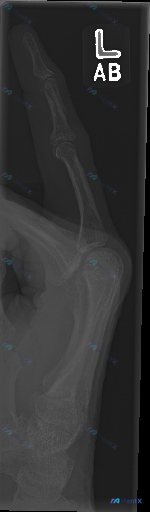

整理到一份左手第一掌指关节区域的侧位X光影像资料,先放出来和大家讨论一下。

影像报告里明确说:

- 骨皮质连续,未见透亮骨折线、脱位或半脱位

- 关节间隙正常,无骨质破坏或骨膜反应

- 未见明显软组织肿胀或异物影

- 综合结论是「骨骼结构未见明显外伤性/炎症性/肿瘤性病变迹象」

但影像分析里也特别提到了一个点:X光的「阴性」绝不代表「排除所有疾病」。结合临床逻辑推演,反而要警惕一些「高风险假阴性」情况。